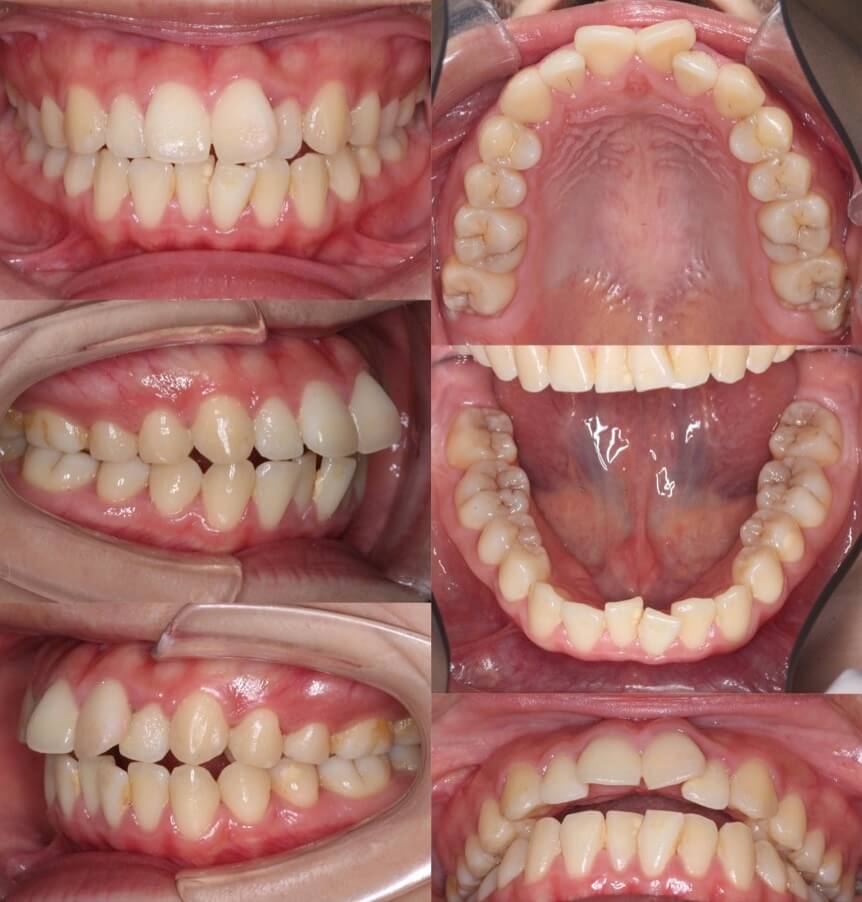

大学生女性・マウスピース型矯正装置・上抜歯

典型的な上のみの抜歯症例です。II級顎間ゴムを使用しながら、ゆっくりと前歯を後方移動させていきました。

<症例概要> 難易度★★★☆☆

主訴:出っ歯

年齢・性別:高校生女性

住まい:千葉県旭市

症状:上顎前突

治療方針:抜歯空隙閉鎖

治療装置:マウスピース型矯正装置(アライナー装置)

抜歯:上左右第一小臼歯(計2本)

治療期間:2年4か月(1週間交換)

アライナー枚数:47+37+16ステージ

リテーナー:上下フィックスタイプ+クリアタイプ

治療費用:990,000(税込)

代表的副作用:痛み・治療後の後戻り・歯根吸収・歯髄壊死・歯肉退縮

▶︎その他の副作用

【治療シミュレーション】

先に上の犬歯のみ抜歯スペースに引き、途中から残りの前歯も後ろに引きます。

※マウスピース型カスタムメイド矯正歯科装置は完成物薬機法対象外の矯正装置であり、医薬品副作用被害救済制度の対象とはならない可能性があります。